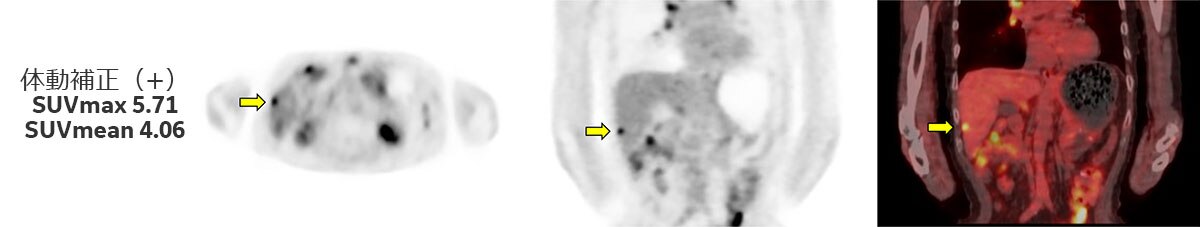

上記とは別症例になりますが(Fig.4)、体動補正を行う事で病変部がより明瞭となっているだけでなく、SUV測定結果では体動補正無しでSUVmax 4.06、SUVmean 3.09だったものが、体動補正を行う事によりSUVmax 5.71、SUVmean 4.06とSUVの上昇も認められています。